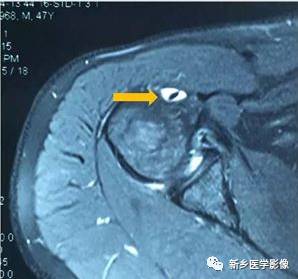

病例三:

红色箭头:肱骨头后方骨缺损(Hill-sachs损伤)

黄色箭头:关节盂前下方Bankart损伤